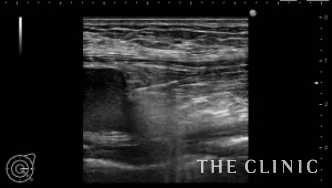

大胸筋の隙間にカニューレを挿入してしこりに到達させ、ベイザーで崩します。

ベイザーで崩した後は、吸引除去します。